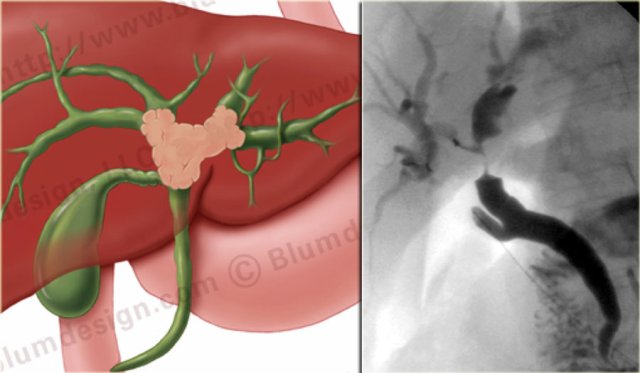

On the left a nice correlation between an illustration and a sonographic image of a Klatskin tumor.

Notice how ill-defined the tumor is.

On CT these tumors can be very difficult to visualize.

Many of these patients already have a stent in place when they first come to CT which makes it even harder (figure).

The staging is done with cholangiography and is based on the finding of mass effect (shouldering), irregular margins and abrupt tapering at the obstruction.

The limitations of MRCP in staging are the spatial resolution and the inability in the evaluation of the secondary ducts.

ERCP is superior to MRCP (figure)

On the left an illustration and ERCP of a type IV-tumor with extention into the right and left duct.

A type IV tumor is unresectable.